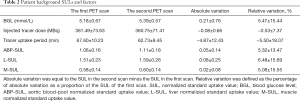

Thirty patients [19 males and 11 females, 20–80 (49.80±15.42) years] were included based on the inclusion and exclusion criteria. They included 11 with lymphoma, 7 undergoing cancer screening, and 12 with other malignancies. The mean time interval was 1–4 (2.23±1.04) days for the two scans. There were no significant variations between the two scans concerning the BGL, injected dose, and tracer uptake period (all P>0.05). Similarly, there were no significant variations between the two scans concerning any of the background SULs (all P>0.05). Tables 1 and 2 give an overview of patient characteristics, SULs, and factors.

Full table